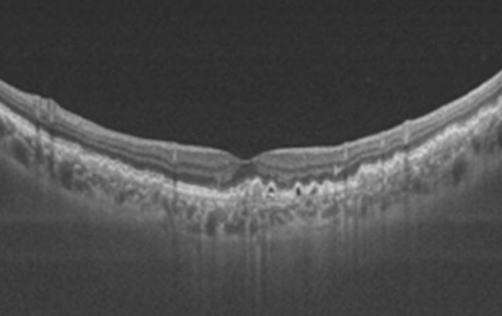

一名57岁的女性糖尿病患者,糖尿病病史12年,既往无眼科疾病。患者因近期双眼逐渐视物不清伴右眼视物变形5年(曾被患者忽视)到眼科就诊。眼科检查显示:右眼最佳矫正视力0.2,左眼0.4。双眼眼前节检查未见异常。眼底检查可见双眼黄斑至周边区域散在均匀的黄色小型玻璃疣,并伴有中心凹反光消失(图1)。

图1. 眼底照片显示双眼多处对称分布的玻璃疣,中心凹反光消失。